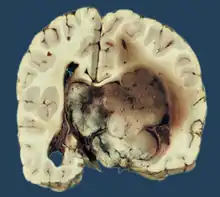

Micrograph of a choroid plexus papilloma. H&E stain.

Plexuspapillom Detail

Plexuspapillom Overview

Histopathology

The tumor is neuroectodermal in origin and similar in structure to a normal choroid plexus. They may be created by epithelial cells of the choroid plexus. Papillary fronds lined by bland columnar epithelium are visible under the microscope. Normal absences include mitotic activity, nuclear pleomorphism, and necrosis.[10] Tumors have positive immunohistochemistry for cytokeratin, vimentin, podoplanin, and S-100.[11] Up to 20% of choroid plexus papilloma patients may test positive for glial fibrillary acidic protein (GFAP).[12] Studies have found that fourth ventricle cancers express more S100 than lateral ventricle tumors, and older patients (over 20 years) express more GFAP and transthyretin than younger patients.[13] Some individuals with choroid plexus papilloma have germline TP53 gene mutations, according to genetic analyses.[14] These cancers rarely exhibit nuclear p53 protein positivity. Aicardi syndrome, hypomelanosis of Ito, and 9p duplication are syndromic correlations of choroid plexus papilloma.